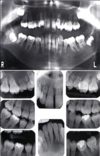

3 radiographic findings of cleidocranial dysplasia

A

• Prolonged retention of deciduous teeth

• Mulitple unerupted supernamary teeth resembling premolars

• Maxillary hypoplasia